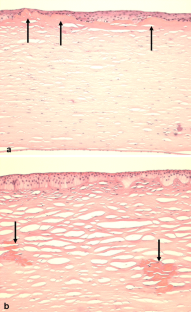

By TEM well-developed hemidesmosomes anchored the basal epithelial cells to the underlying basement membrane in all normal and LCD corneas. Hemidesmosome density was not significantly different in subepithelial (224.7 ± 34.1/100 µm) and stromal (234.3 ± 36.3/100 µm) LCD compared to controls (241.3 ± 26.8/100 µm). The basement membrane was interrupted in subepithelial, but continous in stromal LCD. Integrin α6 and ß4 staining formed a continous line along the basal surface of the corneal epithelium in control corneas, whereas it appeared discontinous and patchy both in subepithelial and stromal forms of LCD. Staining for αV integrin showed irregular staining patterns, i.e. enhanced labelling intensity in subepithelial and interrupted pattern in stromal LCD, respectively. Integrins α3, ß1, ß2, and ß5, dystroglycan, and plectin were not markedly different in dystrophic corneas. Type VII collagen showed a discontinuous staining in subepithelial forms of LCD. In stromal forms of LCD, type VII collagen staining occurred in additional patches underneath the epithelial basement membrane zone. Type XVII collagen staining was reduced in subepithelial LCD. Laminin-1, laminin-5 and laminin γ2 showed variable irregular staining patterns in dystrophic corneas with focal interruptions, focal thickenings, and reduplications of basement membrane. Some irregularities in corneas with subepithelial amyloid were observed for collagen types IV, V, and XVIII, laminin α1, α3, and γ1, nidogen-1 and -2, perlecan, fibrillin-1.